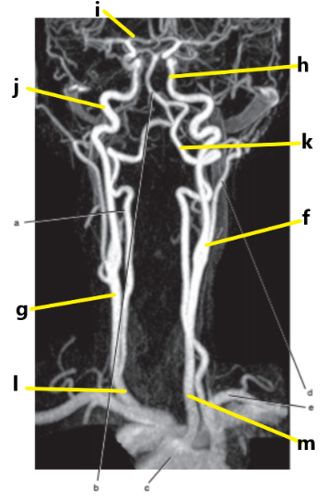

What is letter i ?

Anterior cerebral artery

What is letter j ?

Internal carotid artery

What is letter g ?

Common carotid artery

Vertebral artery

What is letter c ?

What is letter h ?

Internal jugular vein

What is letter k ?

What is letter m ?